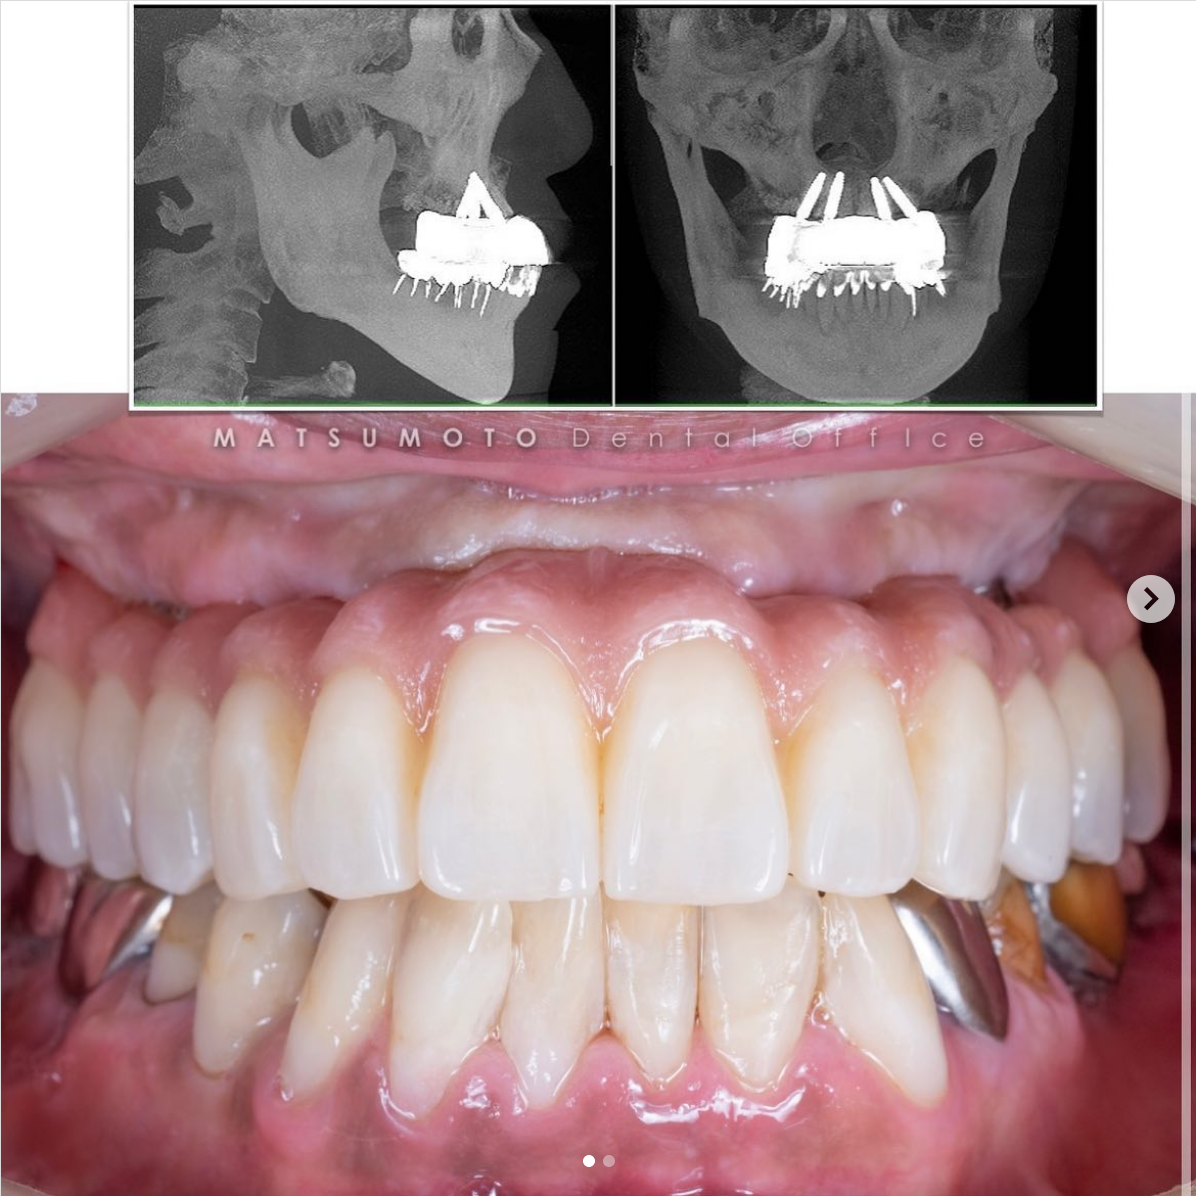

症例紹介27:インプラント治療/下顎6本《70代男性》

患者情報:70代男性

治療内容:

保存不可能なインプラントを抜去して、新しいインプラントを入れ変えました。

インプラントが良い位置に入ってることにより、安定した予後が期待できます。

インプラントガイドを使用することによってこのような結果を出すことができます。

術前の診査診断

術前写真

上顎:インプラントが不適切な位置に入っており、仮歯を無理やり入れている状態。

下顎:インプラント周囲の骨がなくなっており、保村不可能な状態。

パノラマX線

上顎:インプラントは保存できる状態。

下顎:インプラントを含め全て保存不可能な状態。

All-on-6を終えて

最終補綴

上顎:ロケーターアバットによる義歯

下顎:フルジルコニアブリッジ

治療のリスクと副作用

治療期間:約半年

治療費:¥3,850,000(税込)

リスク:インプラントのネジが緩むことはありますが、なるべく連結しないような設計にしているので、問題をはやく見つけやすくしております。